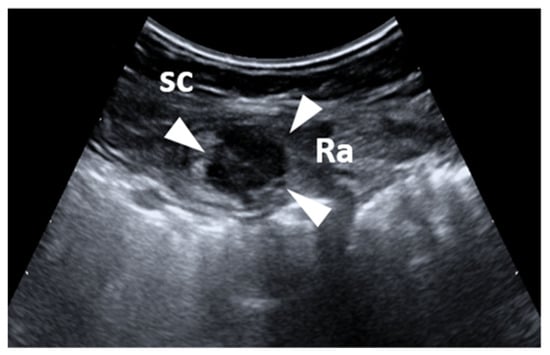

- Cocco, G.; Ricci, V.; Boccatonda, A.; Schiavone, C. Focused ultrasound for the diagnosis of non-palpable endometriotic lesions of the abdominal wall: A not-uncommon surgical complication. J. Ultrasound 2020, 23, 183–187. [Google Scholar] [CrossRef] [PubMed]